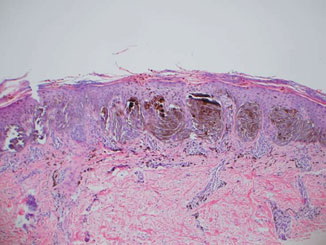

The lesions are usually 3 to 6 mm in diameter, deeply pigmented, and either flat or slightly raised. Most patients are young adults, and the most common location is on the lower extremities. Pigmented spindle cell nevi are uncommon after the age of 35 years. A classic presentation is that of a newly evolved black plaque on the thigh of a young woman. Because of the heavy pigment and the history of sudden appearance, a diagnosis of melanoma is often suspected clinically. In contrast, Spitz nevi are usually submitted with a benign clinical diagnosis, such as an angioma or a dermal nevus. Like Spitz nevi, the lesions are generally stable after a relatively sudden appearance and a short-lived period of growth. Histopathology. The pigmented spindle cell nevus is characterized by its relatively small size and its symmetry and by a proliferation of uniform, narrow, elongated, spindle-shaped, often heavily pigmented melanocytes at the dermal-epidermal junction . The nests of spindle cells are vertically oriented and tend to blend with adjacent keratinocytes rather than forming clefts as in Spitz nevi. Eosinophilic globules (Kamino bodies) may be present . The tumor cells often form bundles that are separated by elongated rete ridges. In the papillary dermis, the nevus cells lie in compact clusters, pushing the connective tissue aside. Numerous melanophages are characteristically diffusely present within the underlying papillary dermis. Involvement of the reticular dermis, common in Spitz nevi, is unusual in pigmented spindle cell nevus. Some lesions show upward epidermal extension of junctional nests of melanocytes. Single-cell upward invasion of the epidermis in a pagetoid pattern may be present but is usually not prominent . Features that may lead to a diagnosis qualified as atypical pigmented spindle cell nevus include architectural abnormalities including poor circumscription and pagetoid melanocytosis, prominent cytologic atypia, or a prominent epithelioid cell component . There may also be considerable overlap with dysplastic nevi . The significance of these atypical variants appears to lie in their greater chance of being misdiagnosed as melanoma because all reports of pigmented spindle cell nevi emphasize their benign behavior after excision. |